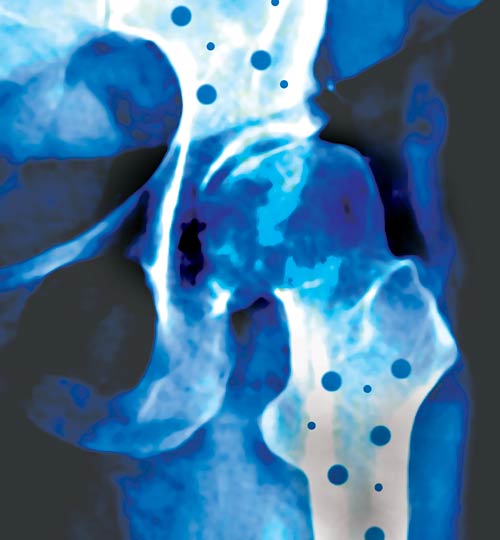

La osteoporosis es una enfermedad ósea de curso crónico, caracterizada por una disminución de la masa ósea y el deterioro de la microarquitectura del hueso. Esto provoca la fragilidad ósea y el aumento del riesgo de fractura. Las regiones mas afectadas son vértebras, muñecas y cadera . Dentro de los factores de riesgo, la menopausia precoz es uno de los mas descrito en la literatura considerando que los estrógenos tienen un rol protector sobre la densidad mineral ósea (DMO). Esta es la definición que dieron a SALUD las reumatólogas Olga Leal, Ana Bazano y Doralía Vázquez, quienes realizaron estudios epidemiológicos en Tucumán, tanto en la población femenina como en la masculina.

La osteoporosis es un problema de salud pública a nivel mundial. Afecta a más de 200 millones de personas y se calcula que entre el 30 y el 50% de las mujeres posmenopáusicas desarrollarán esta enfermedad. Conociendo que la población de más de 65 años aumenta el 1% por año; que la tasa de mortalidad que sigue a una fractura de cadera es un 20% más alta dentro del primer año; que un 10% de las mujeres se hacen dependientes luego de una fractura; que el 19% requiere cuidados domiciliarios, que menos del 50% retornan a sus actividades habituales y que los costos directos e indirectos que genera esta patología son altísimos, se hace necesario elaborar pautas de diagnóstico, prevención y tratamiento que permitan atenuar los efectos sobre la salud pública que produce la osteoporosis desde el punto de vista médico, social y financiero.

Los conferencistas precisaron que en estudios realizados en la Argentina, utilizando densitometría axial en 2 sitios anatómicos (columna y cadera), revelan que una de cada cuatro mujeres mayores de 50 años de edad son normales; dos de cada cuatro tienen osteopenia (inicio de la afección) y una de cada cuatro tienen osteoporosis en por lo menos un área esquelética (columna lumbar o cuello femoral).

En nuestro país se realizó una docena de estudios epidemiológicos sobre incidencia de fracturas de cadera: dos se publicaron en forma completa, y cuatro han sido parcialmente comunicados en congresos. En promedio, ocurren anualmente 298 fracturas cada 100.000 mujeres de más de 50 años de edad, y 117 fracturas cada 100.000 varones de dicha edad.

La Organización Mundial de la Salud (OMS) define a la fractura osteoporótica (fractura por fragilidad) como aquella que resulta de una fuerza o torsión que se ejerce sobre el hueso, y que sería insuficiente para fracturar el hueso normal.